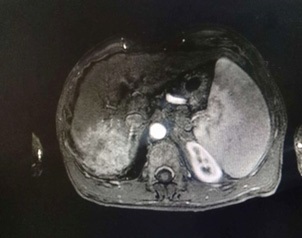

The patient, a 55-year-old male, was admitted to the hospital on March 11, 2021 due to “upper abdominal distension, pain and discomfort for more than 1 year, and recurrence for more than 2 months”. More than 1 year ago, the patient had no obvious inducement of upper abdominal distension, pain and discomfort, no acid reflux, heartburn, no nausea, vomiting, no hemesis, melena, no chest pain, chest tightness and other discomfort, no care, no diagnosis and treatment. Before 2 months, the patient’s symptoms were aggravated again, and the symptoms continued to be not relieved, so the emergency department was admitted to our hospital as “abdominal distension cause check”. Previous healthy, smoking and drinking history, no similar patients in the family. Improve relevant examinations after admission, such as: Infectious disease screening: hepatitis B surface antigen (gold standard method) positive (+), HBVDNA: 3.89 x 106 IU/ml, TAP: 128.03 um², liver function:TP: 50.23 g/L ALB: 27.8 g/L, TBIL: 34.8 g/L, DBIL: 15.00 g/L, IBIL: 19.8 g/L, ALT: 27 g/L, AST: 51 g/L, PCHE: 1879 g/L, AFP: 203.8 ng/ml, Color Doppler ultrasonography of chest and abdomen showed that liver cirrhosis was possible, portal vein velocity decreased, liver disease gallbladder, splenomegaly and splenic vein dilation. 256 row chest and upper abdomen CT (plain scan + enhanced): 1. Ground glass shadow of left lung, follow-up and reexamination are recommended; 2. Liver cirrhosis, splenomegaly, esophagogastric fundus and splenic collateral circulation; The abnormal enhancement focus in the right lobe of the liver, considering the high possibility of liver cancer, the remaining small nodule like enhancement in the liver, considering intrahepatic metastasis (Figure 1). 3. Gastric antrum space occupying, considering malignancy, please combine clinical and pathological findings. 3.0 Mr upper abdomen (plain scan + enhancement): 1. Liver cirrhosis with regenerative nodules, splenomegaly, portal hypertension, ascites and collateral circulation; 2. Abnormal signal of right posterior lobe of liver (Figure 2). Considering malignancy, please combine clinical and AFP examination. Gastroscopy showed: 1. Esophageal gastric fundus varices (severe); 2. Gastric antrum space occupying: Ca? (Figure 3); Gastric antrum pathology (HE staining Figure 4) results: (gastric antrum) adenocarcinoma. Liver puncture pathology (immunohistochemical (Figure 5) diagnosis: (liver puncture) combined with immunohistochemical results, it is consistent with hepatocellular carcinoma. Immunohistochemistry: CerbB2 (0), CK (+), HEPA (partial +), glypican (+), CD (small amount +), CD34 (blood sinus +), CK7 (-), CK8 (+), CK19 (-), CDX2 (-), Ki67 (50% +), GS (+), CK20 (-). Physical examination: Body temperature was 37OC, pulse was 78 beats/ min, respiration was 20 beats/min, blood pressure was 120/70 MHg, skin and mucosa of the whole body were mildly yellow, no rash, bleeding spots, liver palm or spider nevus, superficial lymph nodes were not touched and enlarged, and no obvious abnormalities were found in head, neck, heart and lungs during physical examination. Abdominal distention, soft abdomen, no obvious tenderness, rebound pain and muscle tension in the abdomen, liver, spleen and ribs are not touched, negative mobility dullness, bowel sounds are normal. The patient refused interventional therapy, asked for oral chemotherapy and was discharged after her symptoms improved.

Figure 2: MRI results of upper abdomen (plain scan).